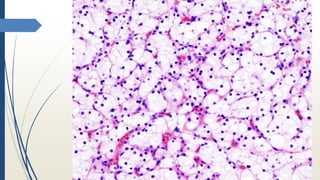

ANGIOMIOLIPOMA

LUIS HUMBERTO CRUZ CONTRERAS

Tumor Benigno

• Grasa

• músculo

• Vasos gruesos

50% esporádicos

• Únicos

• Grandes

• Asintomáticos

50% Sclerosis Tuberosa

• Múltiples

• Bilaterales

Macroscopía

• NO encapsulados

• Color amarillo

• Hemorragia

Microscopía

• GRASA, MUSCULO LISO, Y VASOS GRUESOS

• Pueden presentar pleomorfismo leve

• Pueden extender a la vena renal

• Variante EPITELIODE (MÚSCULO)